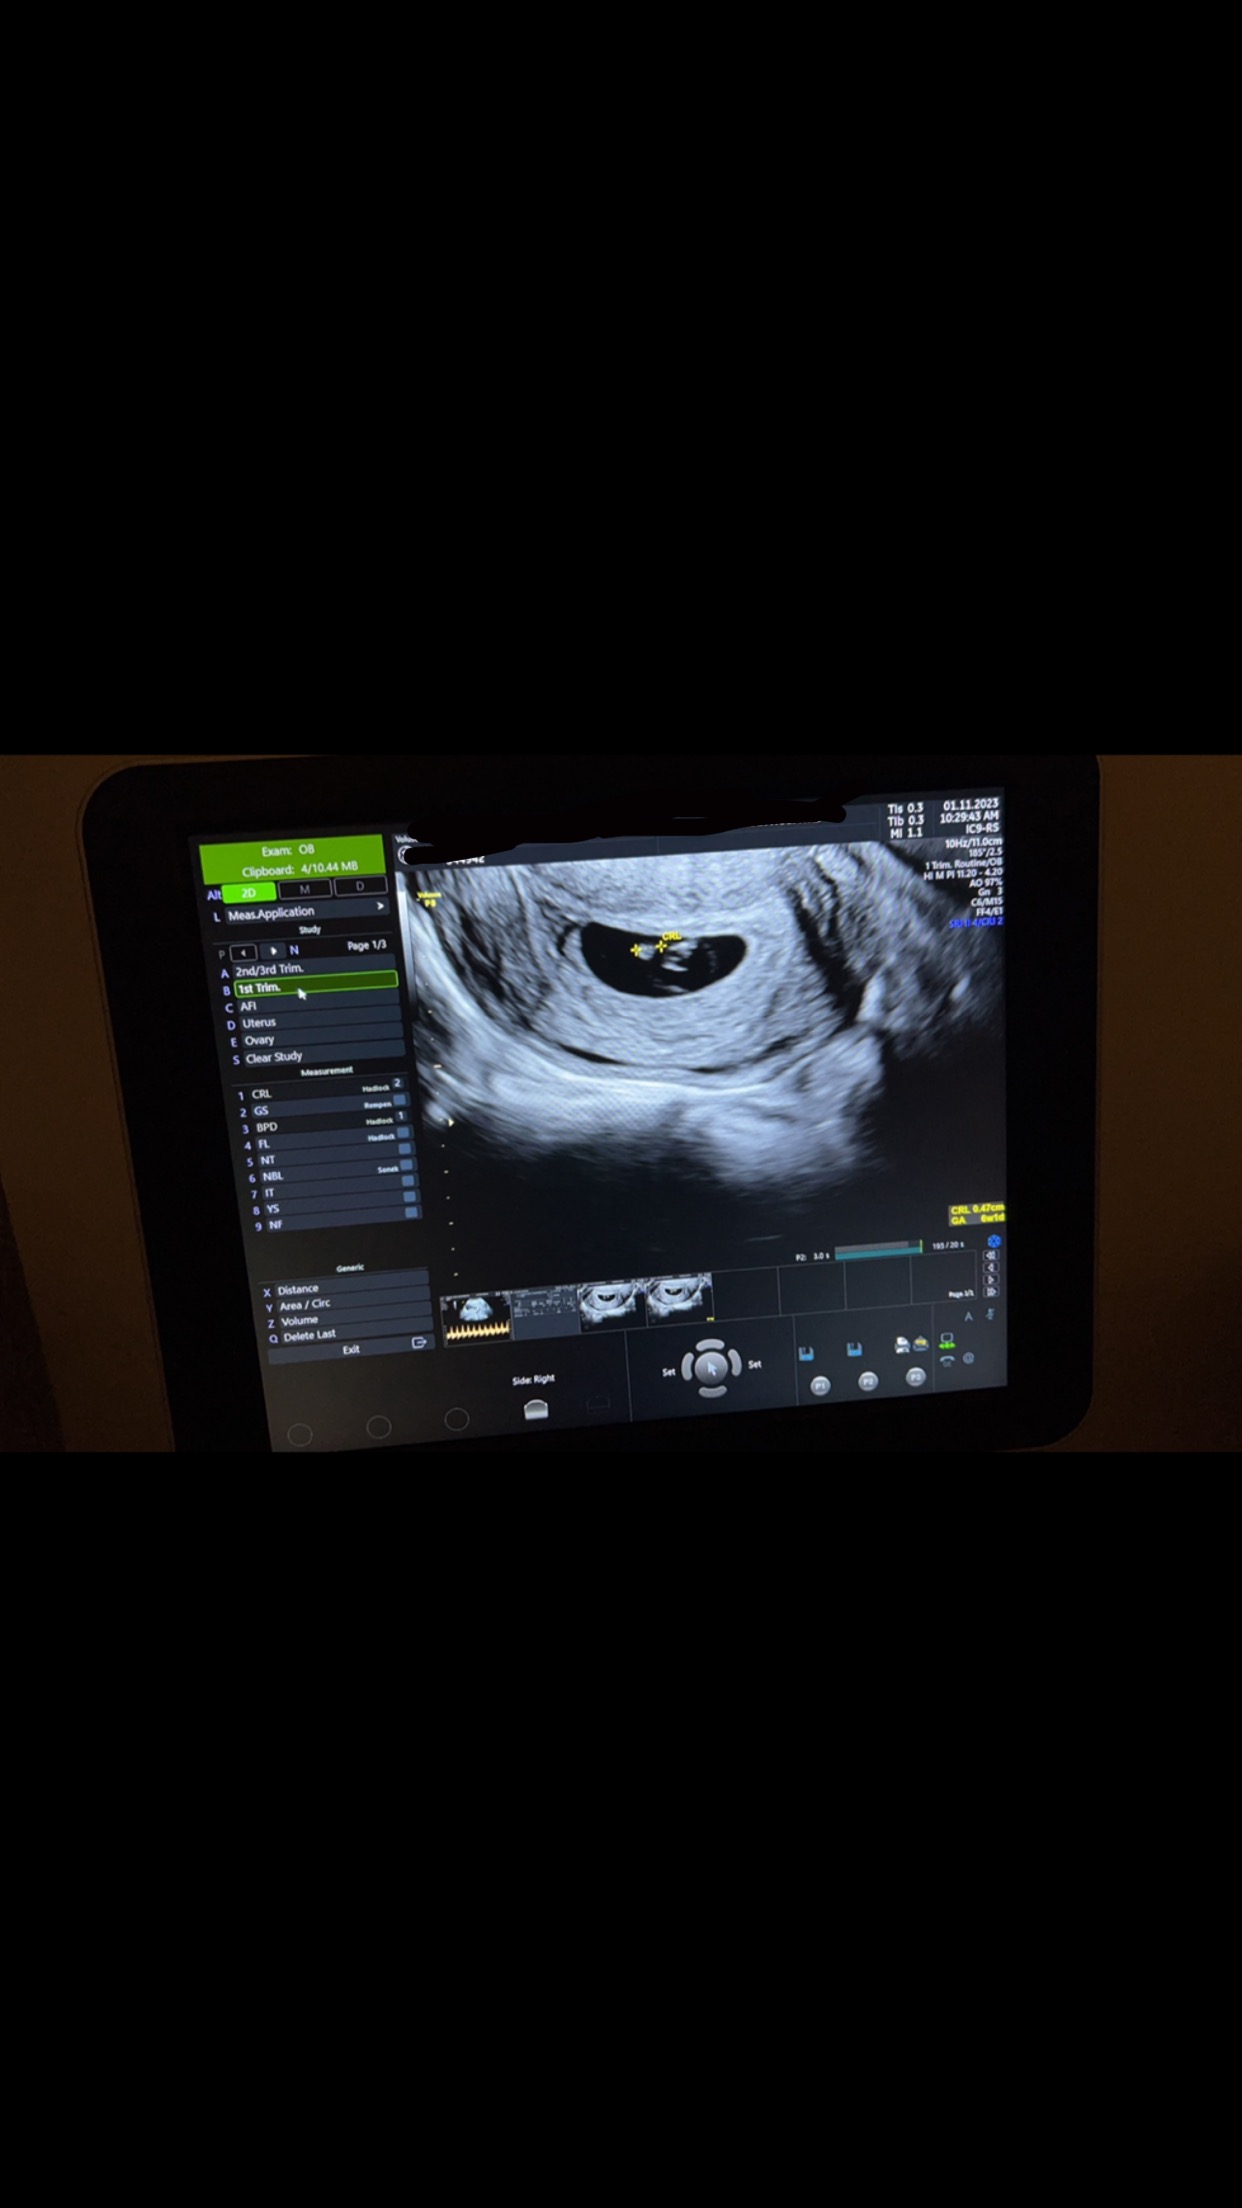

نبض الجنين ما مبين هل هذا الشي طبيعي